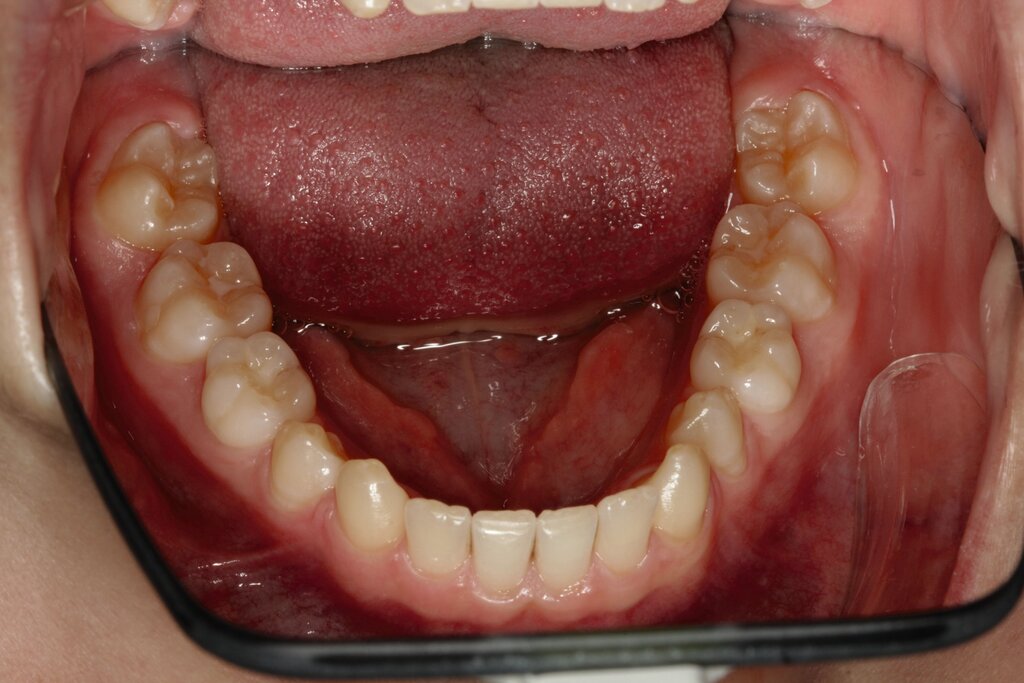

Bei dem gut zwölfjährigen Mädchen sind die seitlichen oberen Schneidezähne (Zähne 12 und 22) nicht angelegt. Zusätzlich zeigten sich verlagerte zweite obere Prämolaren.